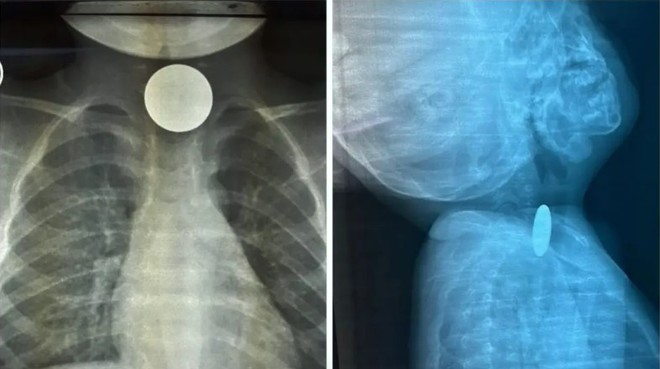

رابغ ہسپتال میں سکہ نگلنے والے دو سالہ بچے کو بچالیا گیا

دو سالہ بچے کو رابغ جنرل ہسپتال ایمرجنسی وارڈ لایا گیا تھا (فوٹو: العربیہ)

سعودی عرب میں رابغ جنرل ہسپتال کے طبی عملے  نے سکہ نگل لینے والے دو سالہ بچے کو یقینی موت سے بچالیا۔

العربیہ نیٹ کے مطابق محکمہ صحت جدہ نے بیان میں کہا کہ’ دو سالہ بچے کو رابغ جنرل ہسپتال ایمرجنسی وارڈ لایا گیا تھا۔ بتایا گیا کہ اس نے کوئی چیز نگل لی ہے جس سے اس کا دم گھٹ رہا ہے۔ نگلی جانے والی چیزحلق میں اٹکی ہوئی ہے‘۔

رابغ جنرل ہسپتال کے طبی عملے نے فوری آپریشن کیا۔ پتہ چلا کہ بچے نے سکہ نگل لیا تھا۔ بچے کو ہسپتال سے فارغ کردیا گیا۔